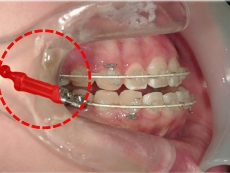

臼歯にリンガルアーチという装置を装着し、ミニインプラントを固定源に臼歯を後方に牽引します。

臼歯が後方に下がり、臼歯と小臼歯の間にスペースができました。唇側にワイヤ-をSETし、前歯の歯並びの改善を併行して行います。